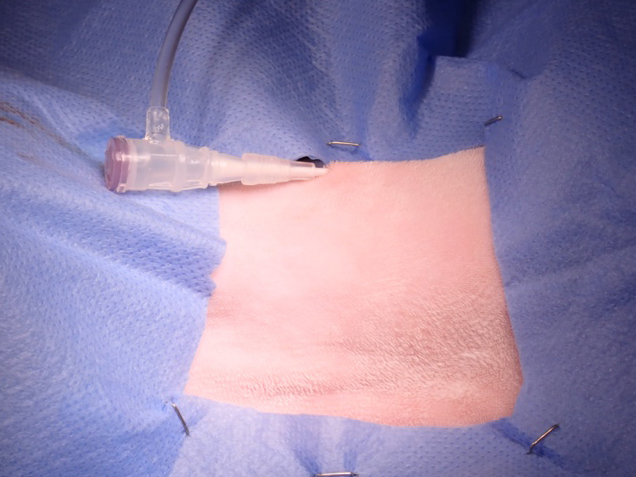

手術中の様子:セルジンガー法

手術中の様子:カテーテル設置後